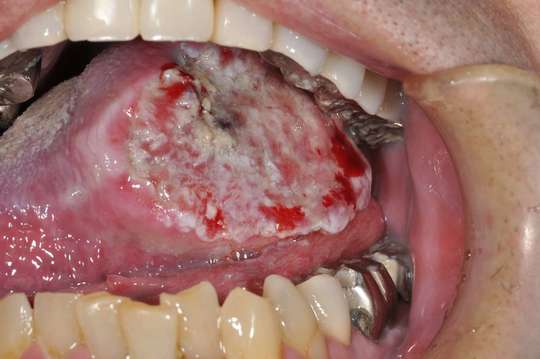

口内炎と口腔癌 舌ガン との違い。

好きです: 296